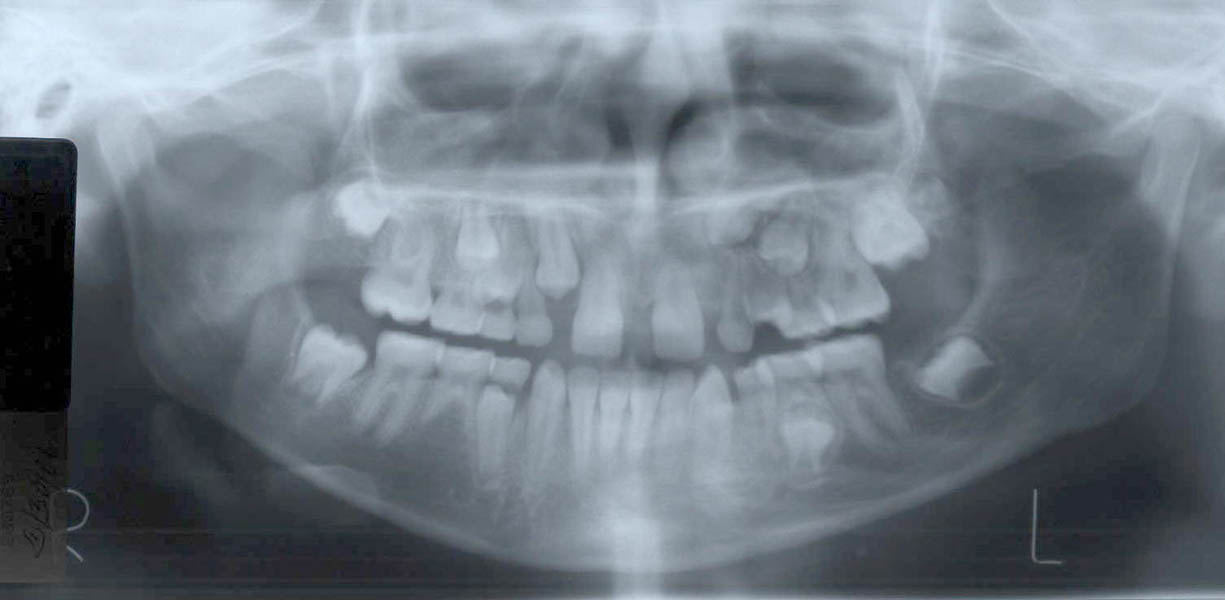

A doua etapă a tratamentului a fost amânată până în aprilie 2006, când pacienta a împlinit vârsta de 11 ani şi 5 luni. În acel moment, fetiţa prezenta erupţie şi dezvoltare radiculară adecvată, astfel că aparatele fixe aplicate acum n-ar fi purtate o perioadă îndelungată. Ocluzia inversă frontală şi angrenajul invers lateral fuseseră corectate; totuşi, exista o diastemă mare, în principal cauzată de lipsa incisivilor laterali superiori (fig.3). În acest moment, radiografia panoramică relevă anodonţia incisivilor laterali maxilari şi a premolarului secund drept mandibular, o anatomie redusă a rădăcinilor incisivilor centrali superiori, incluzia caninului superior stâng şi dezvoltarea întârziată a rădăcinii celui de-al doilea premolar inferior (fig. 4).